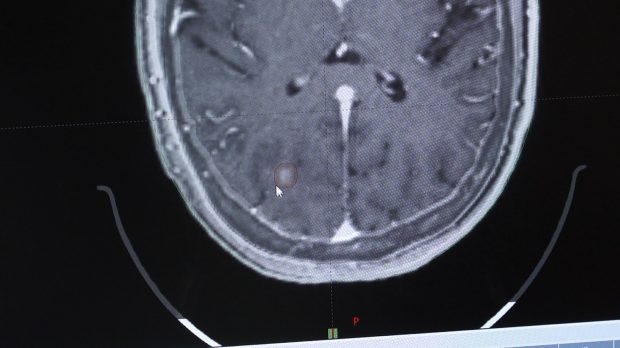

Dr. Jaden Evans, a radiation oncologist at Intermountain Healthcare's McKay-Dee Hospital, started Merrill on stereotactic radiosurgery, a form of high-dose radiation pinpointed to the cancerous tumor, opposed to whole-brain radiation, which used to be the standard.

"You're giving very high doses right into the tumor and you're just avoiding all the normal tissue," he said. "Obviously, you don't want to treat those critical structures and you want to only focus on where the cancer is … so it's targeting that spot precisely."

"He works really hard to make sure that I still have function," Merrill said. "It lets me be me still, because we're only targeting the tumors. We're not targeting the healthy spots in my brain."